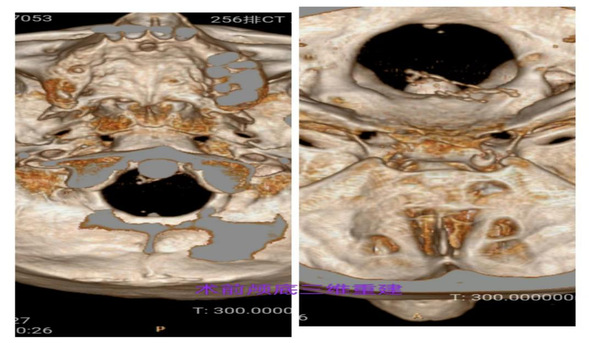

颅底三维CT重建提示卵圆孔形态大小正常